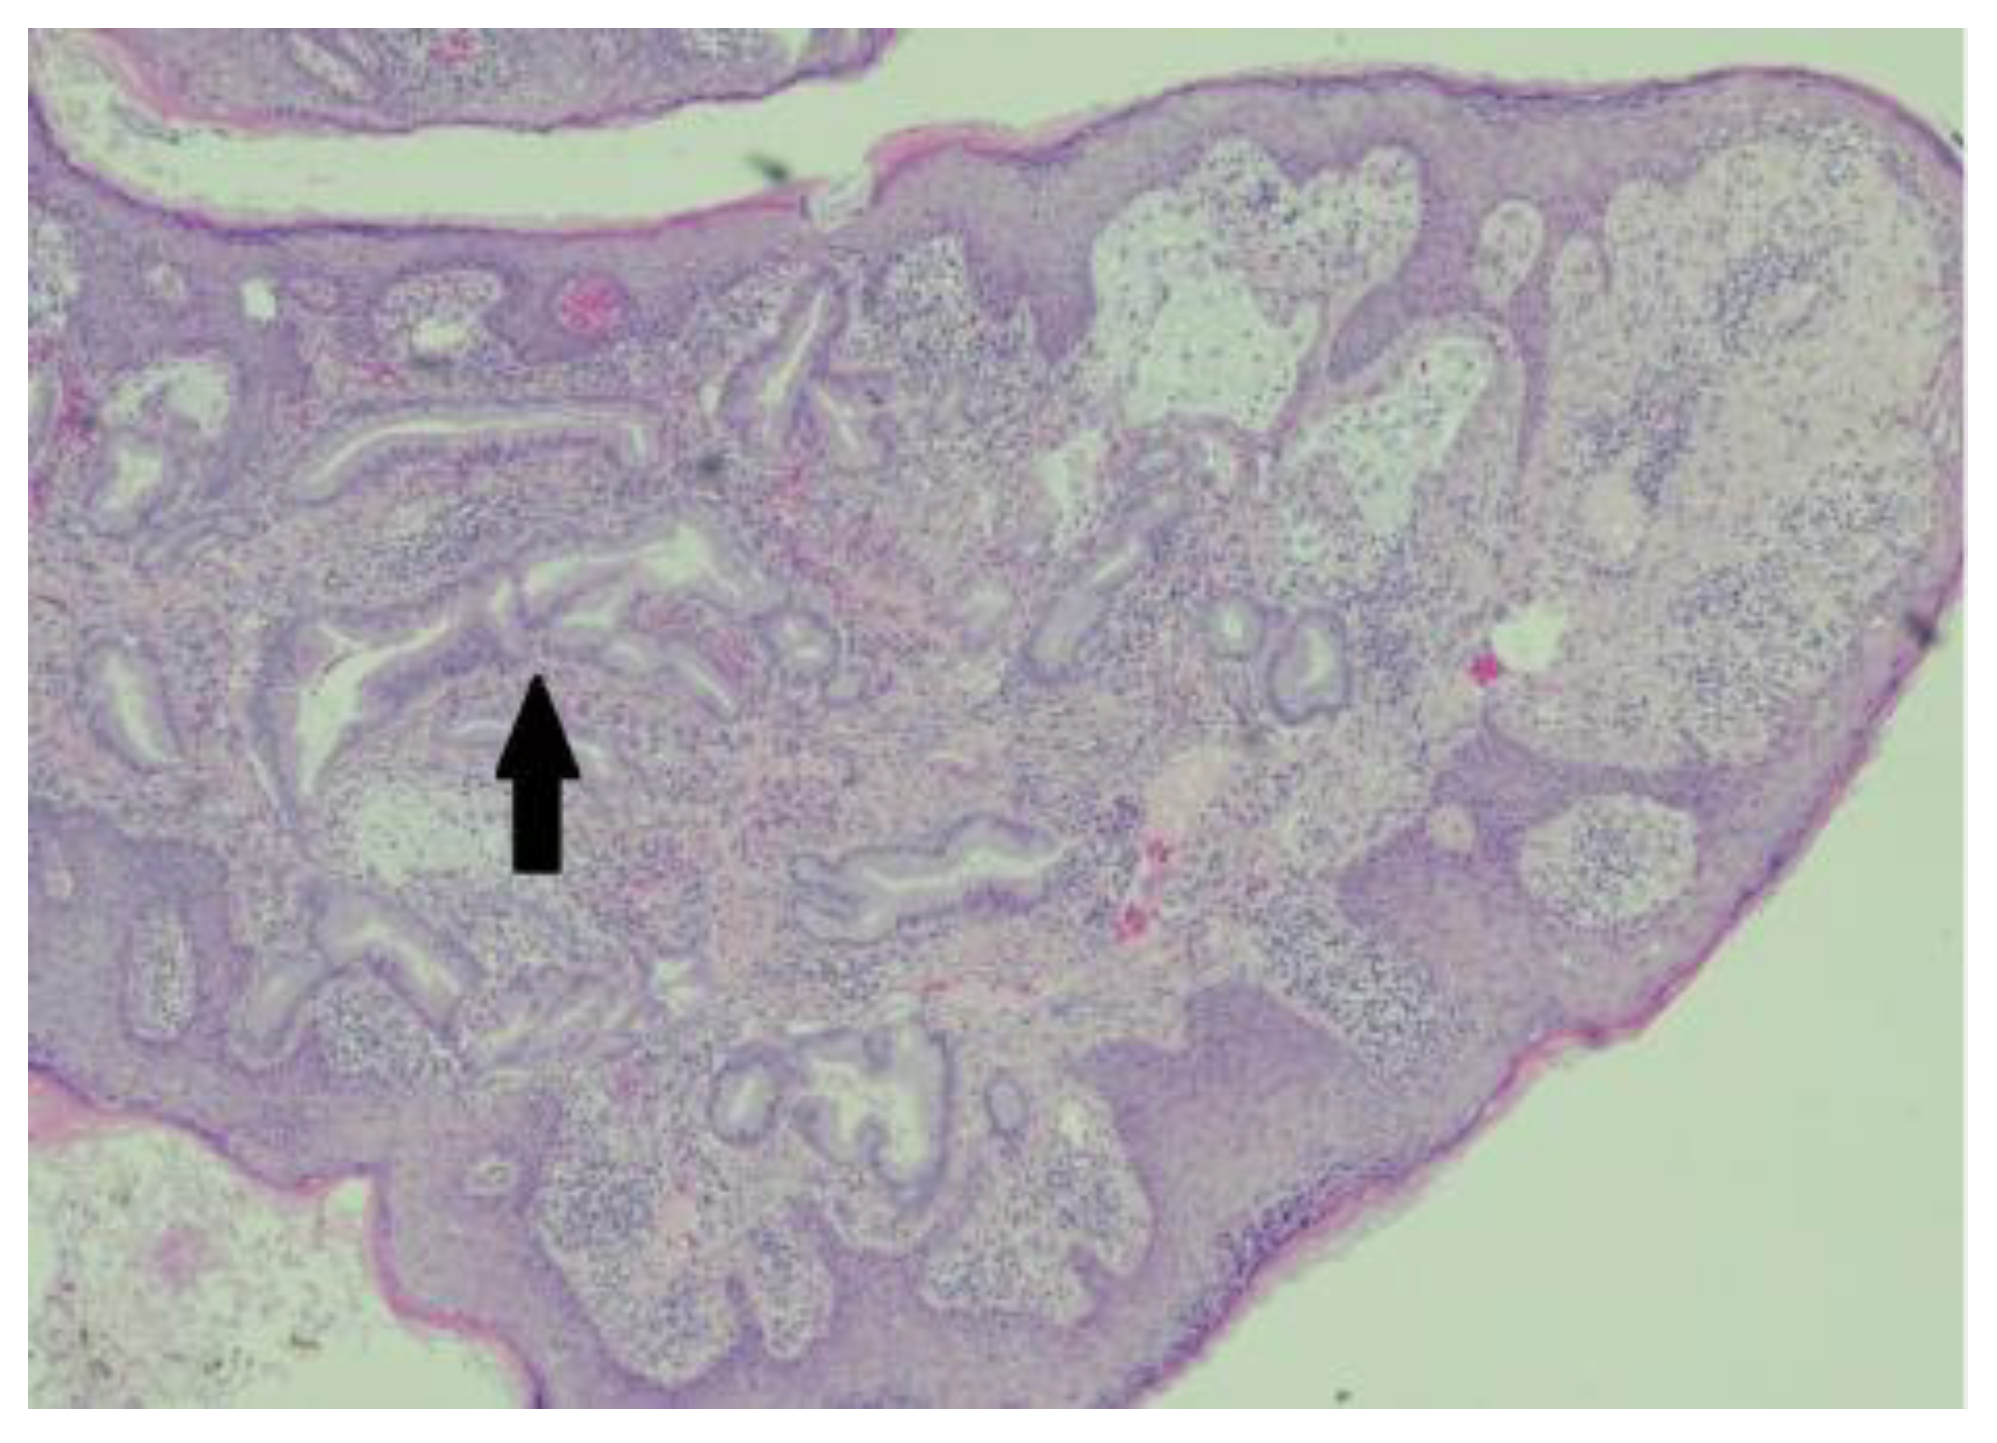

In preparation for the procedure, it was noted that the patient had endorsed lethargy over the past few weeks. Additionally, preprocedural routine labs were notable for a direct bilirubin of 2.93 mg/dL. Due to the polypoid and irregular nature of the lesion, his concomitant lethargy, and direct bilirubinemia, a CT scan of the patient’s abdomen and pelvis was performed, which revealed a distal intrahepatic cholangiocarcinoma with involvement of left hepatic lobe (Figure 1) and umbilical induration corresponding to the skin lesion (Figure 2). A magnetic resonance cholangiopancreatography (MRCP) was performed for further characterization of the cholangiocarcinoma, which revealed an intrahepatic cholangiocarcinoma (Figure 3).

Figure 4. Moderate-power image of the umbilical lesion, showing infiltration of the malignant glands through the papillary and reticular dermis (as indicated by the black arrow) . .